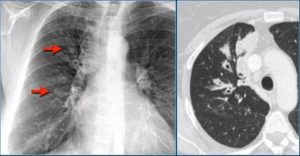

Выявление одиночных очагов в легких. До настоящего времени методом первичного выявления очагов в легочной ткани остается обычное рентгенологическое исследование – рентгенография или флюорография. Одиночные очаги обнаруживаются в 0,2-1,0% всех рентгенологических исследований грудной клетки.

На обзорных рентгенограммах или флюорограммах редко можно выявить одиночный очаг размером 1 см такие контуры служат веским аргументом в пользу злокачественного процесса и, следовательно, показанием для морфологической верификации.

На самом деле, при прохождении флюорографии или рентгенографии сложно выявить ООЛ, размер которого меньше 1 см. Интерпозиция анатомических структур может сделать практически невидимыми и более крупные очаги.

Поэтому большинство врачей советует пациентам отдать предпочтение компьютерной томографии, которая дает возможность рассмотреть ткани в разрезе и под любым углом.

Это полностью устраняет вероятность того, что поражение будет закрыто сердечной тенью, ребрами или корнями легких.

То есть рассмотреть всю картину в целом и без вероятности фатальной ошибки рентгенография и флюорография попросту не может.